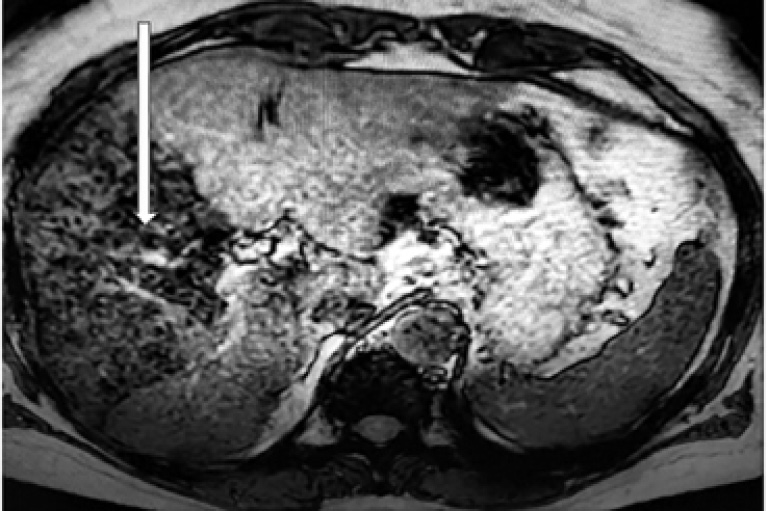

С целью дальнейшей визуализации вводимых клеточных структур в организме пациента предварительно культура аутологичных МСК была обработана наночастицами оксида железа. Через сутки после проведения клеточной терапии пациенту были выполнены МРТ органов брюшной полости и грудной клетки и УЗИ печени (рис. 2, 3).

Рис. 2. МРТ органов брюшной полости через 1 сутки после введения аутологичных МСК в артериальное русло печени. Стрелкой указаны области печени, в которых визуализируются маркированные стволовые клетки

На представленном снимке МРТ органов брюшной полости введенные стволовые клетки визуализируются в правой доле печени. При этом в каких-либо других органах брюшной полости, а также в грудной клетке клеточные структуры не выявлены. При УЗИ печени также удалось визуализировать фиксированные в правой доле меченые клеточные структуры, однако по сравнению с МРТ не представлялось возможным четко определить границы располагающихся МСК.